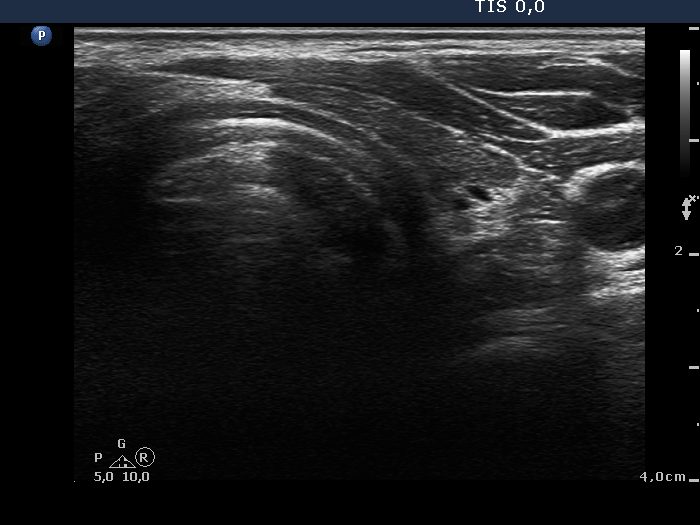

First examination (1st to 3rd rows of images):

Ultrasonography: Both lobes presented hypoechogenic ill-defined areas. The echogenicity index was 80% in the right lobe while 20% in the left thyroid. The vascularization was significantly decreased.

Elastography demonstrated hard areas according to the hypoechogenic field in the left lobe while almost the entire right lobe proved to be hard.Cytological diagnosis: subacute, granulomatous de Quervain's thyroiditis.